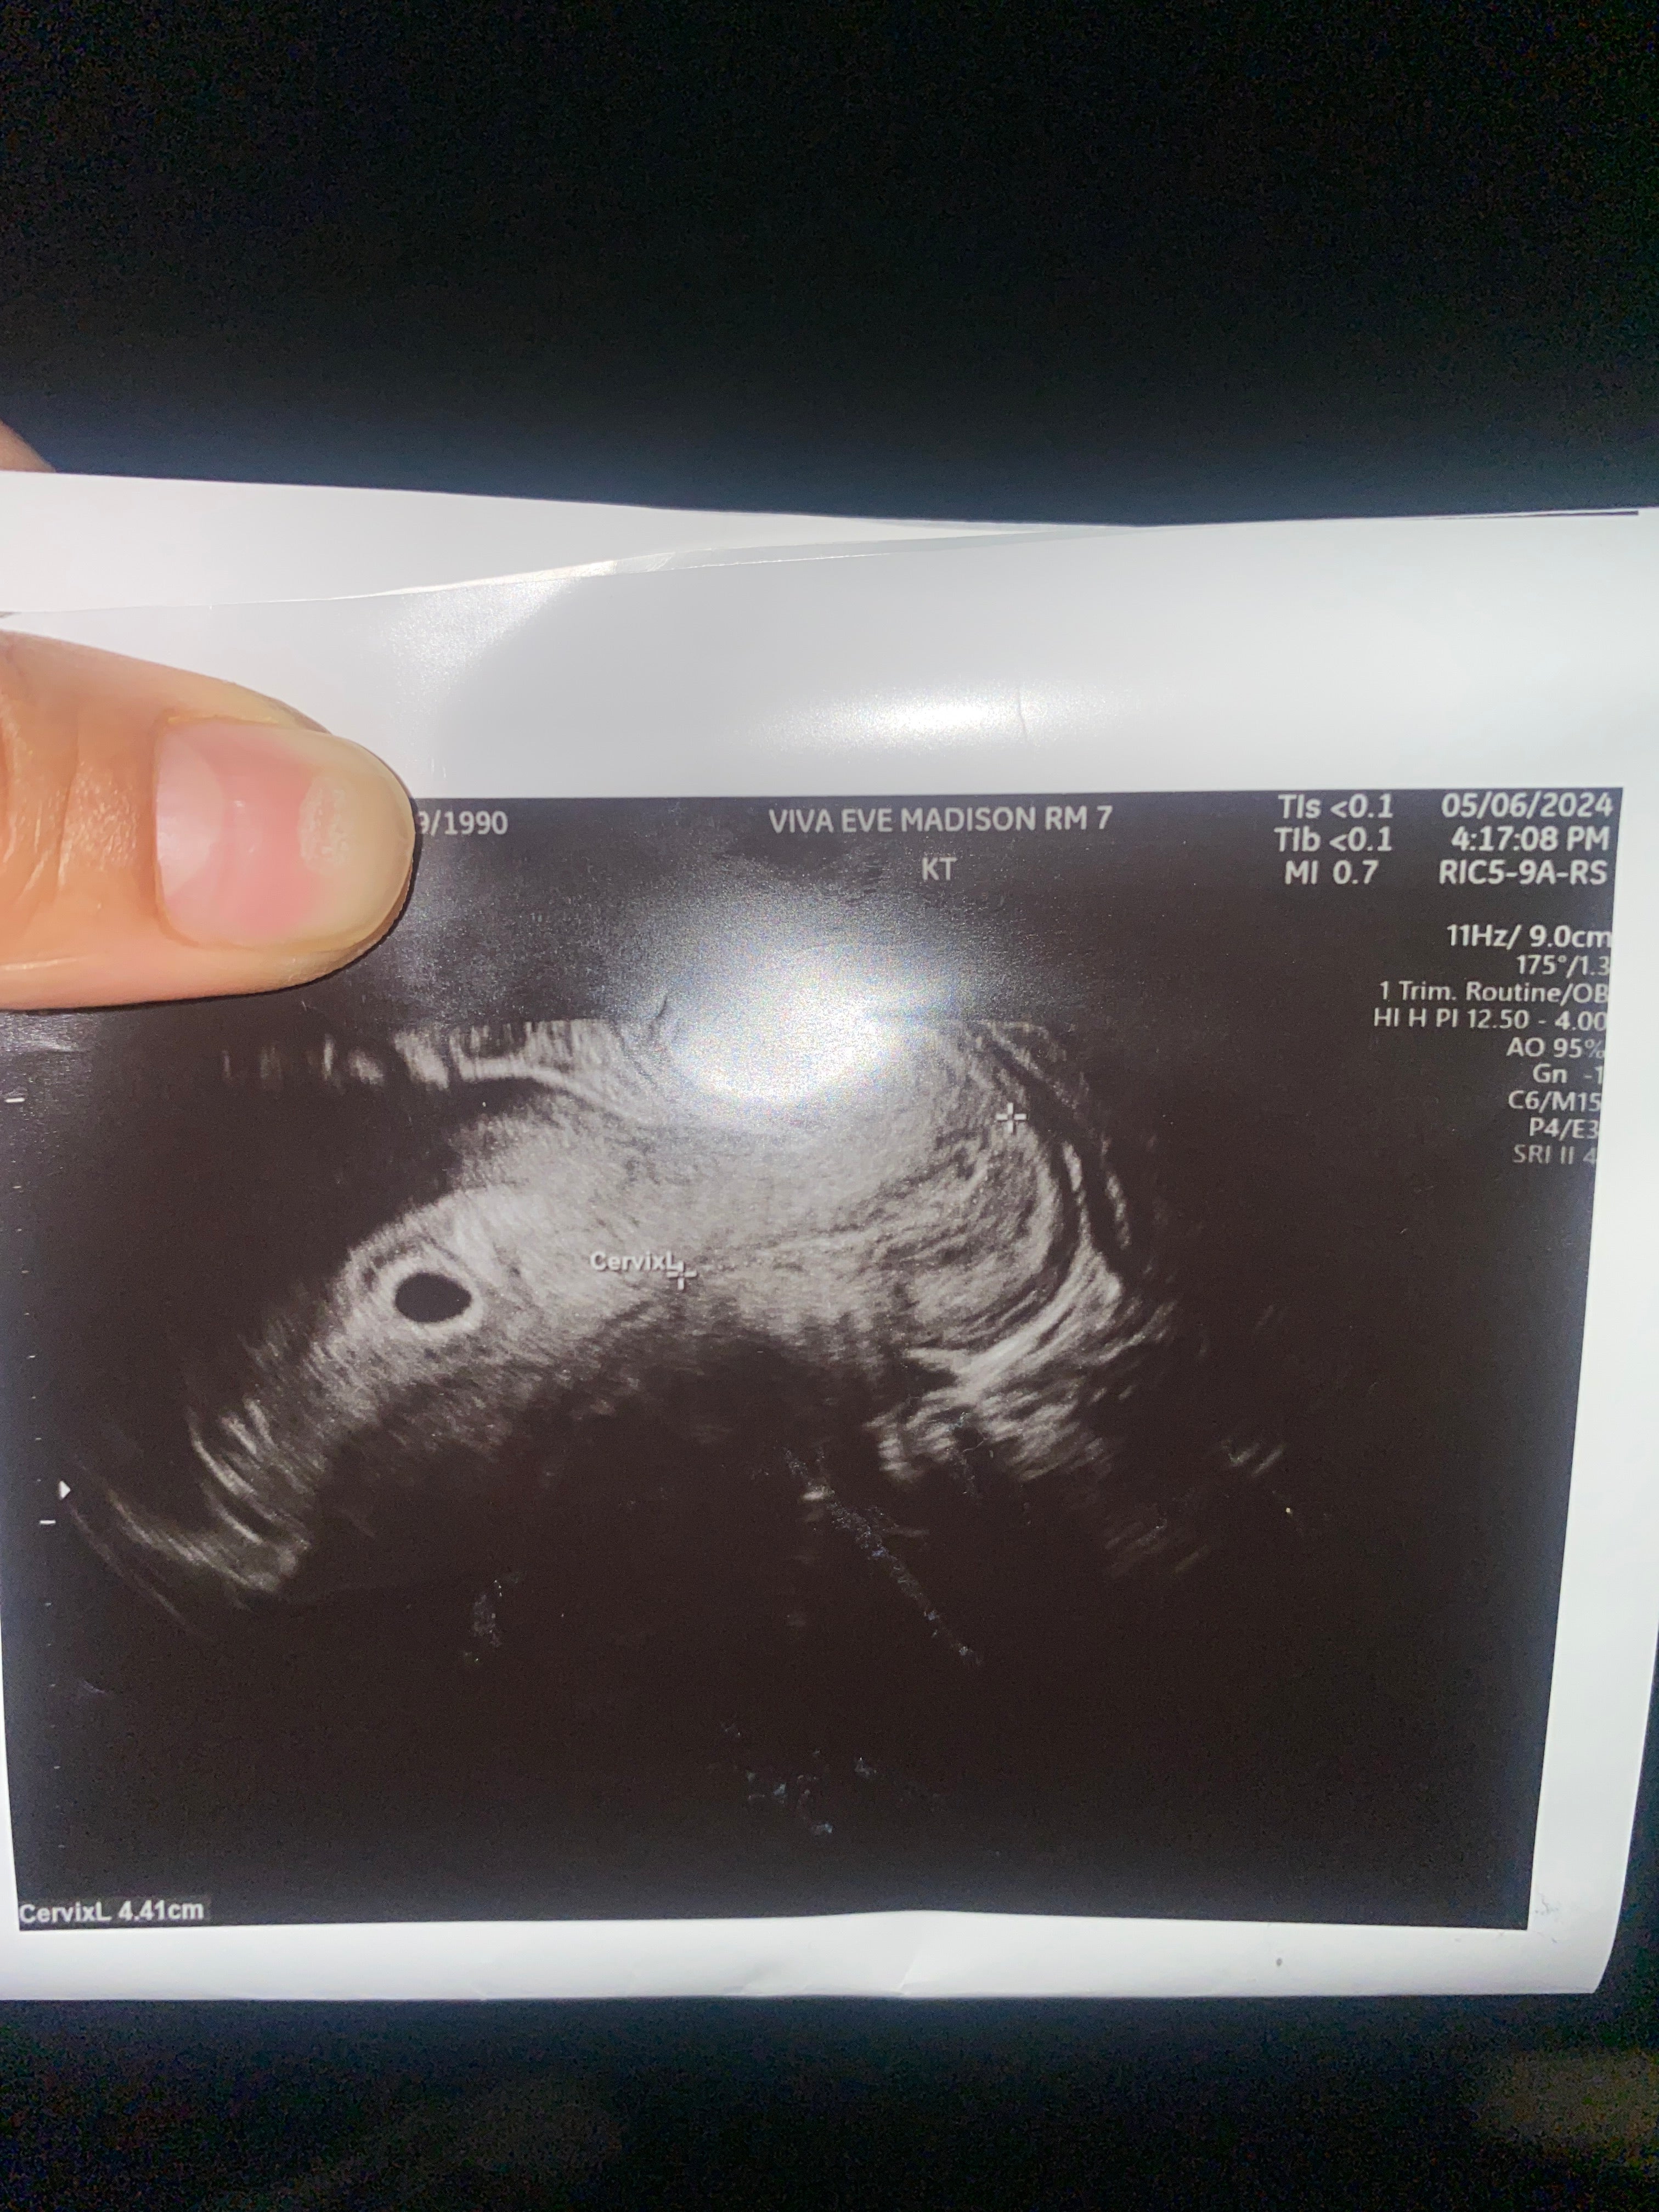

My husband and I have struggled to conceive due to my endometriosis and some scaring tissue that destroyed my right ovary and Fallopian tube. Luckily after a few surgeries I started to get better but was concerned IVF would be out of reach now that I have limited eggs. Mosie Baby made me and my husband have a chance at a normal pregnancy. I am currently now 5 weeks and 4 days pregnant! Thank you Mosie Baby!